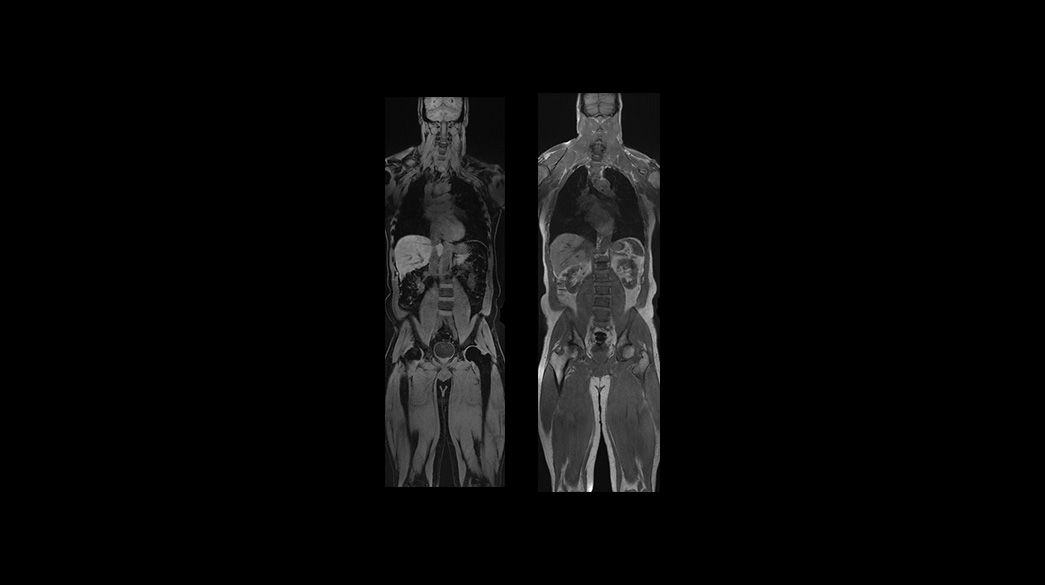

Access and productivity

HyperWorks1040-x-585

Read case study ico-caret-right